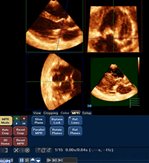

The advanced method, known as multiplane review (MPR) 3D echocardiography, allows the user to identify heart defects much more accurately than on traditional 2D or standard 3D scans and is revolutionising the accuracy and speed of diagnosis.

“The most important aspect is the operator's ability to slice the dynamic cardiac structures in infinite sections through all the three dimensions, which was not possible before we developed MPR 3D echocardiography,” said Dr Vettukattil.

“You can chop the heart into small pieces and see what is wrong and exactly where it is wrong on the screen. By using MPR, because you are slicing and seeing it in three different planes, you can get a clear understanding of a patient – especially in a child whose heart is congenitally malformed.”